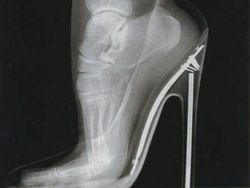

Beginilah tulang kaki wanita ketika menggunakan sepatu hak tinggi. (Foto: Brightside)